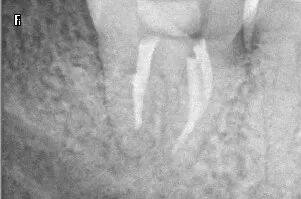

董医生听完郑先生的讲述后,经过反复认真比对牙片,和仔细询问病情,并开展多学科会诊,根据与牙体牙髓科沈旸熠医生的联合诊断,确认他患的是牙周牙髓联合病变。

董医生结合郑先生情况,尽最大可能保住牙齿,最终给出了让患者满意的治疗方案:经过牙周刮治、根管治疗后再进行GTR手术(牙周组织再生手术),最后带上牙冠的方法,尽最大可能保留患者的天然牙。